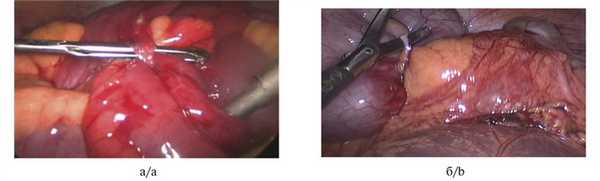

В отсроченном порядке оперированы 10 (22,3%) больных. Показаниями явились рецидивирующее течение спаечной болезни от 2 до 6 раз в течение года и «малые» операции (гинекологические операции, холецистэктомия, аппендэктомия, грыжесечение) в анамнезе. Признаком адекватности проведенного адгезиолизиса было заполнение газом и кишечным содержимым дистальных отделов желудочно-кишечного тракта (рис. 3). Рис. 3. Интраоперационная картина лапароскопического адгезиолизиса (изображение при эндоскопии). а — единичный штранг, выявленный при лапароскопии, который является причиной спаечной тонкокишечной непроходимости; б — рассечение штранга, восстановление пассажа по кишечнику, устранение тонкокишечной непроходимости. a — a single adhesion diagnosed during laparoscopy which resulted adhesive small bowel obstruction; b — intersection of adhesion, restoration of passage through small bowel, elimination of small bowel obstruction.